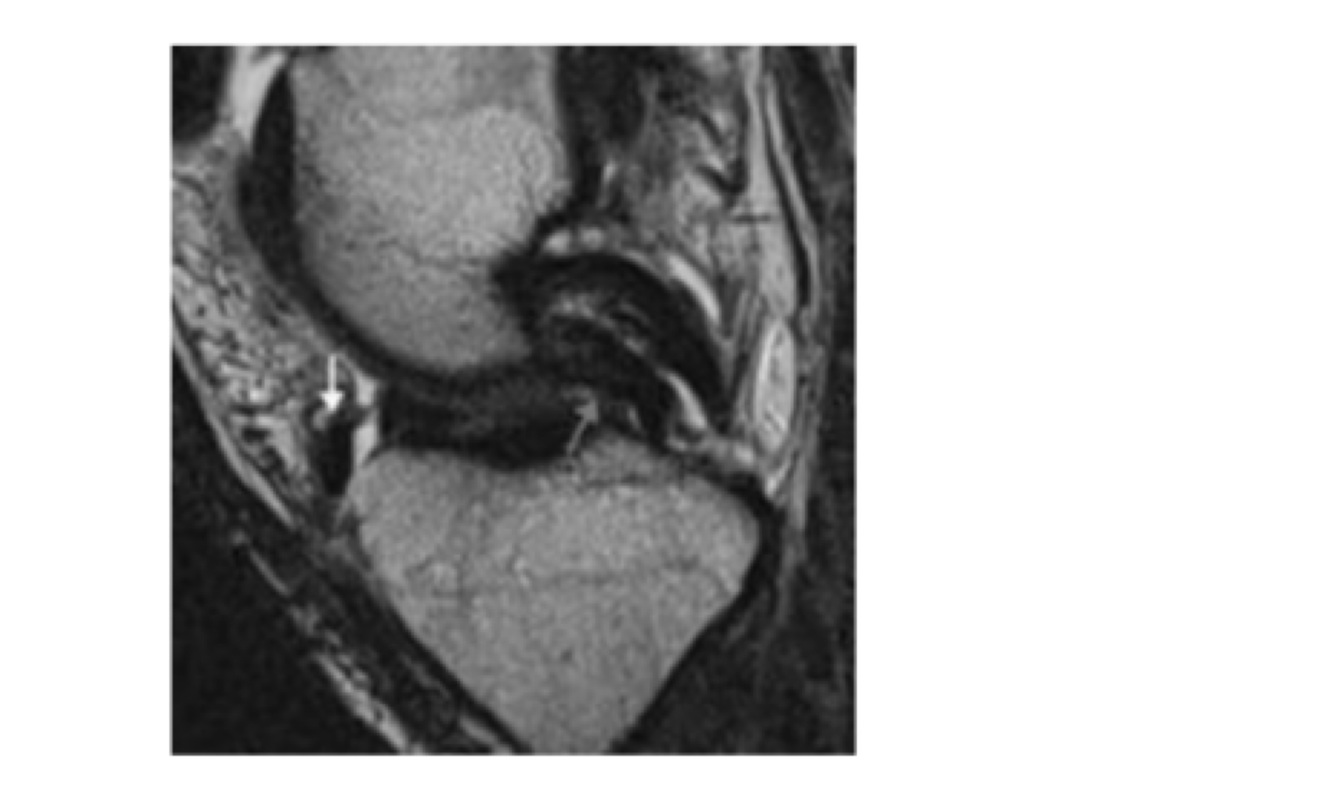

Qual achado?

Duplo contorno do LCP (Patognomônico de alça de balde)

Qual o achado?

Sinal do duplo LCP

(Patognomônico de alça de balde)